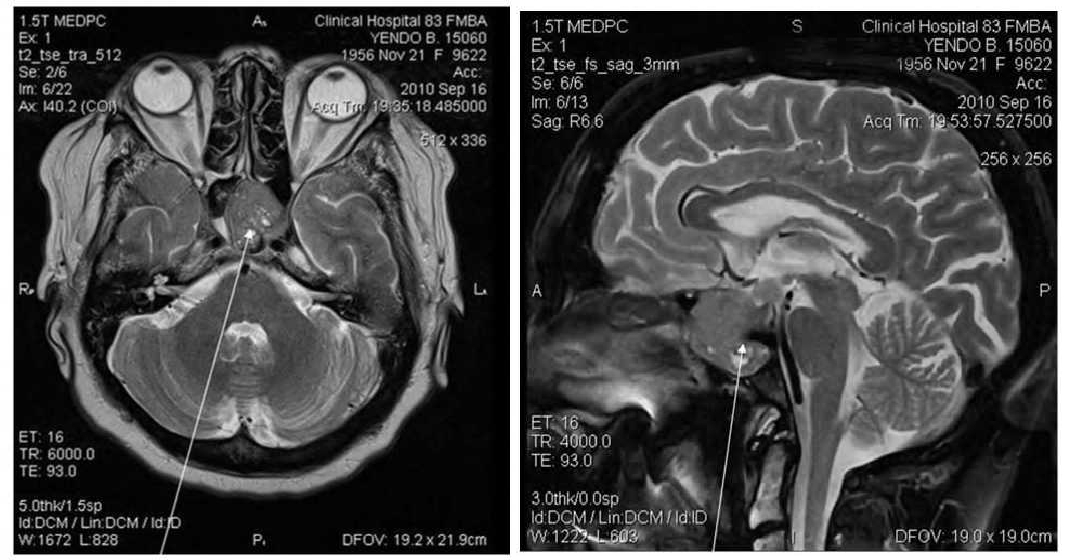

На МРТ головного мозга в 3-х проекциях в полости расширенного турецкого седла выявляется зона изоинтенсивности. Нижним краем опухоль проецируется в основную пазуху,распространяется параселлярно, обрастая сонные артерии, больше справа и прорастает вверх и влево, отдавливая 3 желудочек вправо. Желудочки головного мозга симметричны, увеличены в объеме. Субарахноидальные ликворные пространства неравномерно расширены. Базальные цистерны симметричны, умеренно расширены. Заключение: МРТ картина эндоинфрапара-супраселлярная опухоль гипофиза (рис. 2)

Рис. 2. MPT картина эндо-инфра-пара-супраселлярная опухоль гипофиза